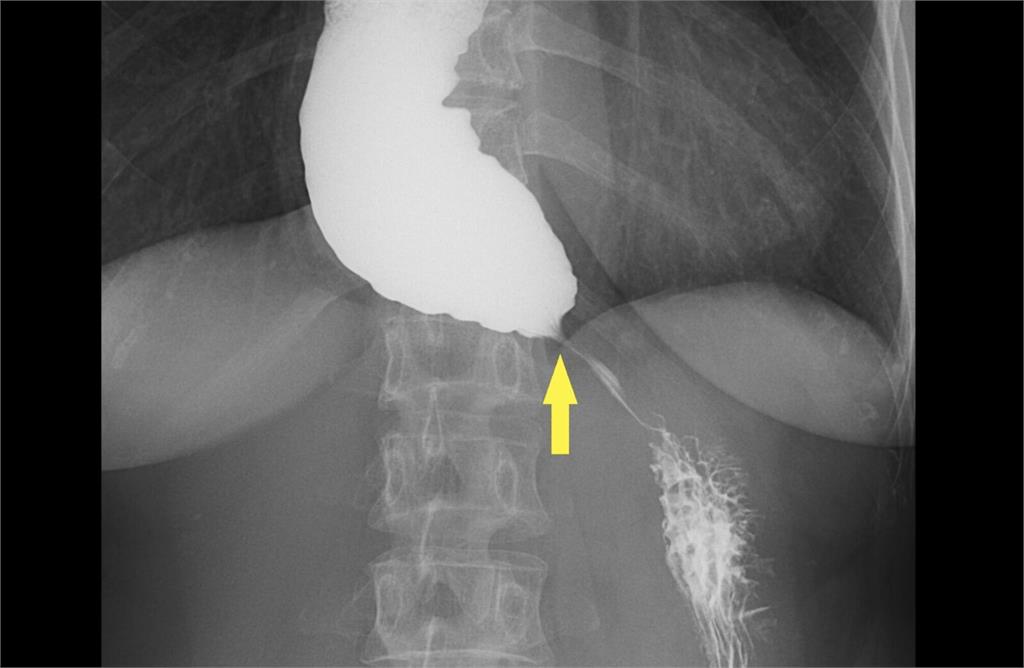

台北慈濟醫院胃腸肝膽科醫師詹崴宇指出,婦人首先接受食道攝影與食道高解析度壓力檢測(HRM),其中食道攝影顯示食道末端出現典型「鳥嘴狀」狹窄,但壓力檢測結果卻沒有典型下食道括約肌壓力上升表現,讓診斷一度陷入兩難,所幸,接著以新式診斷工具功能性管腔成像探頭檢查,終於確診。

詹崴宇說,若長期未接受治療,食道可能因食物堆積而嚴重擴張,形成不可逆的「巨大食道」,即使後續解除下端的出口梗阻,食道上方嚴重擴張卻已無法復原。針對食道弛緩不能症的病患,治療重點在鬆開過緊的下食道括約肌,其中經口內視鏡肌肉切開術在無特殊禁忌下通常為首選,長期有效率高達90%;藥物治療或肉毒桿菌注射的放鬆效果較短暫,多適用於高齡或不宜手術患者;而以氣球撐開狹窄部位的氣球擴張術常因復發而需要接受多次的處理,現今已非首選。